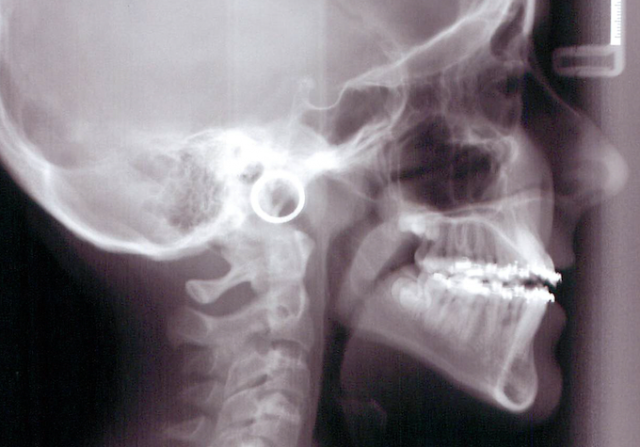

The challenge often lies in controlling the vertical dimension particularly in cases of excess vertical facial height. Vertical control is often linked with controlling the eruption of second molars. I have often heard the question asked why some orthodontists do not bond the second molars. In some cases the decision could be related to vertical control. As the most distal contact and hinge point, any increase in the eruption of the second molar can result in a discouraging anterior bite opening and increased overjet as the mandible rotates down and backward. A heavy wire extended to the second molar can easily accomplish this undesirable result in a vertical growth pattern. (Fig. 1 and 2)